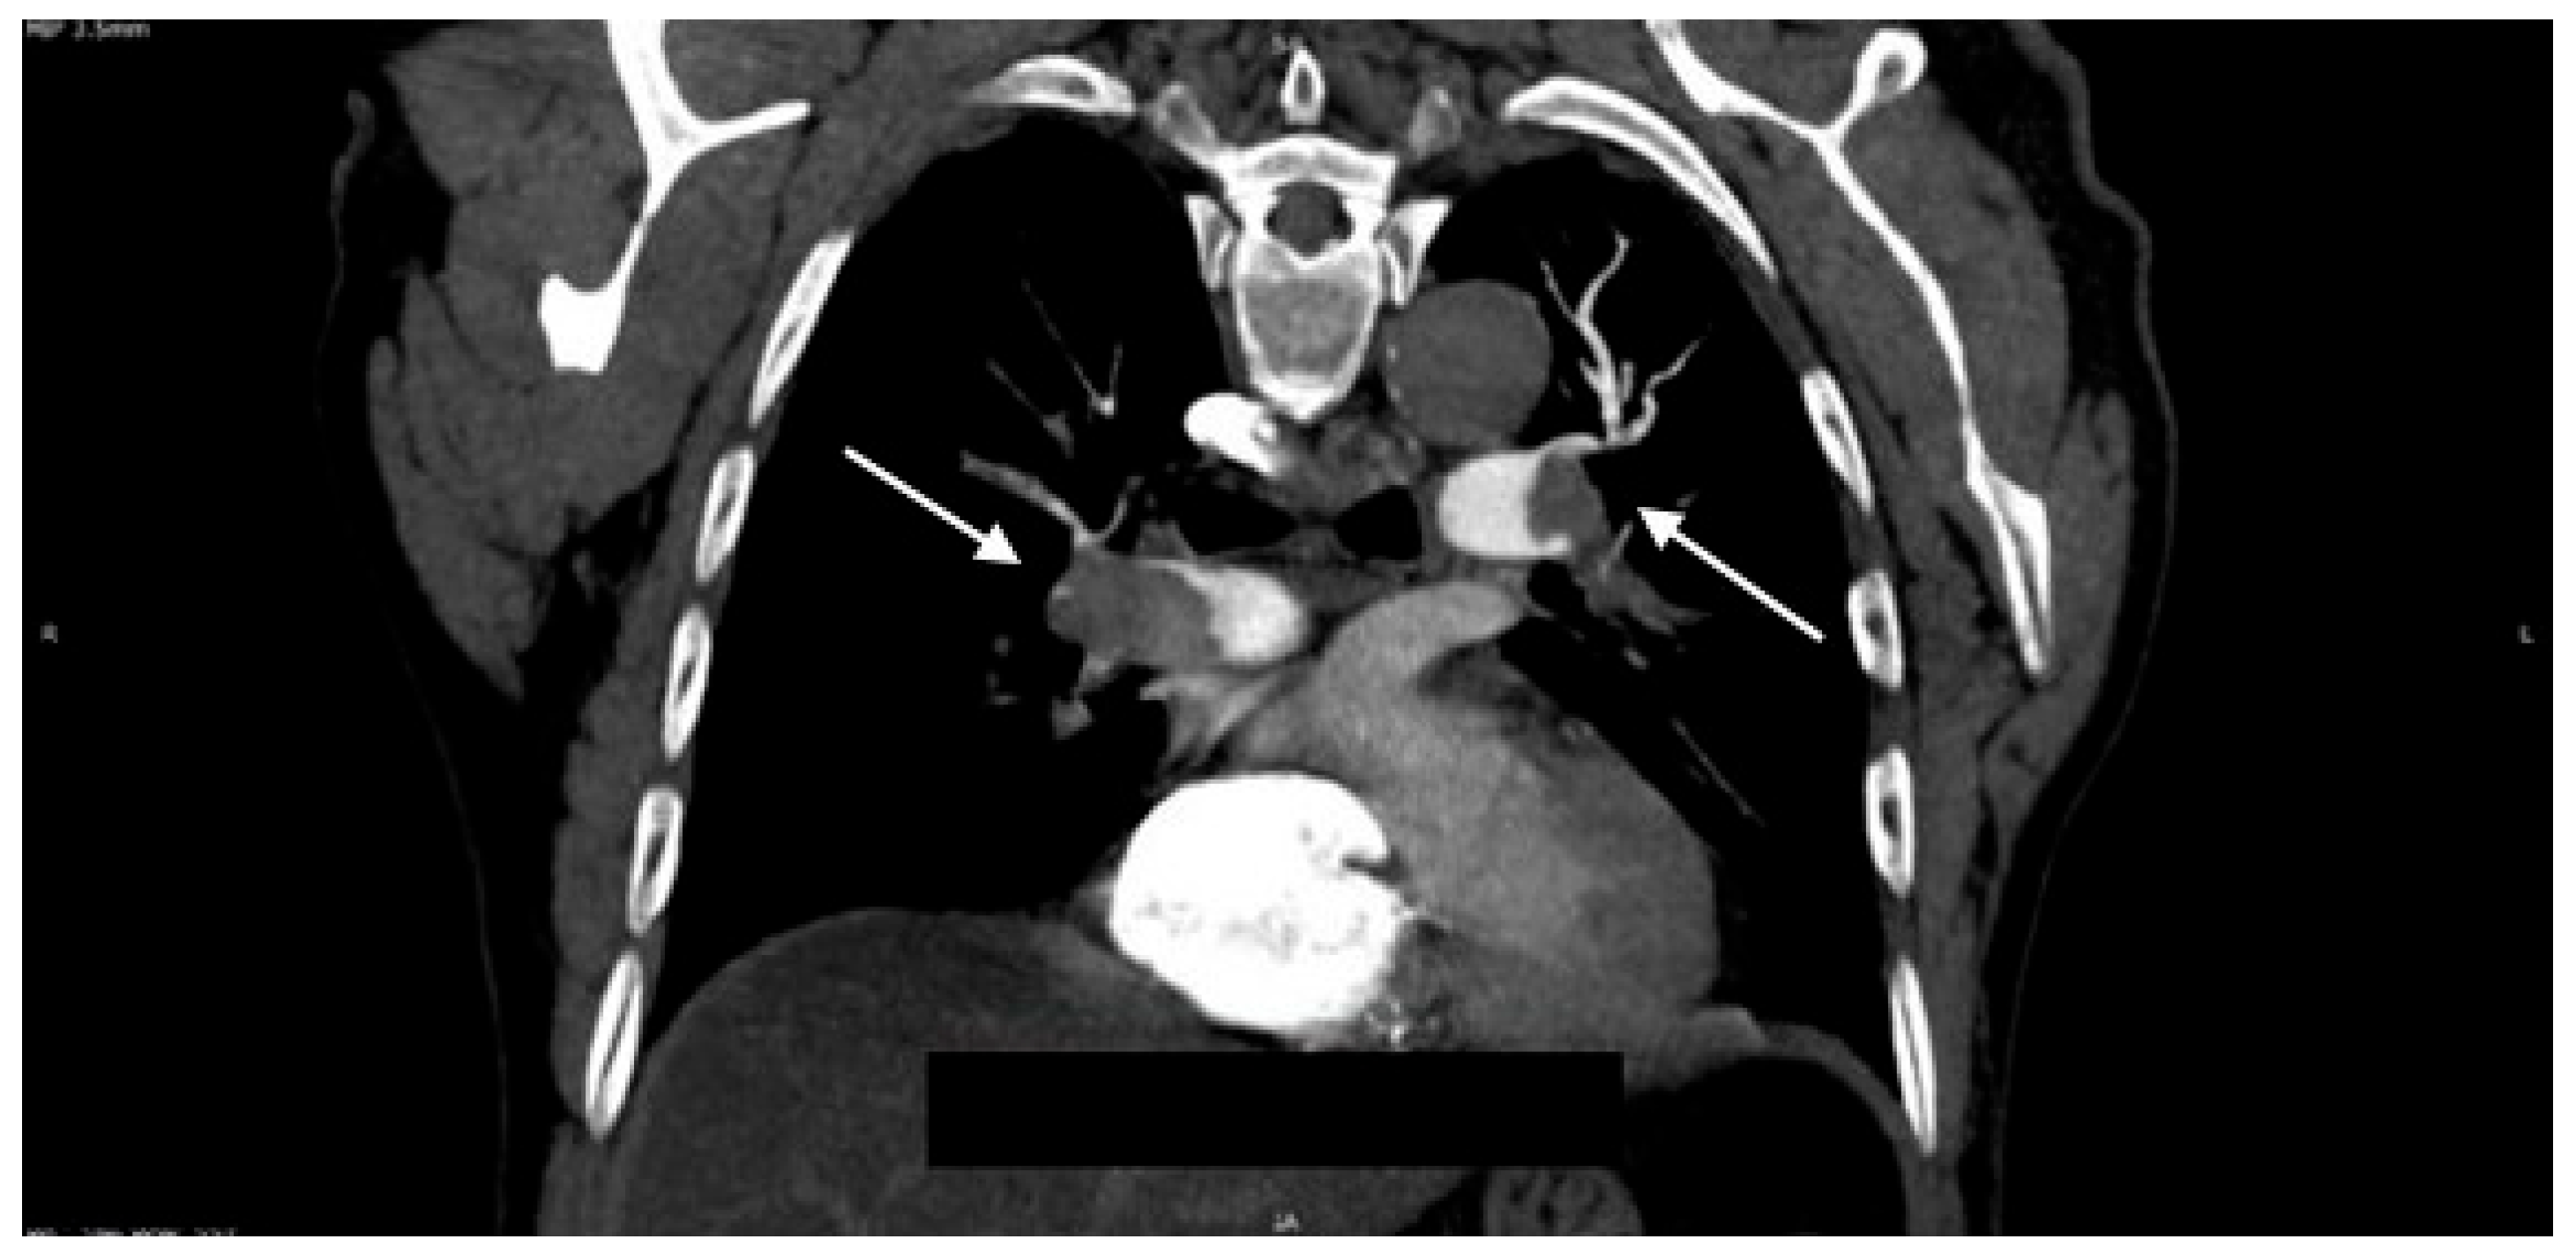

Given that the therapeutic decision depended on the presence or absence of pulmonary embolism and on the extent of vascular involvement secondary to thrombosis, and taking into account the patient’s hemodynamic stability, a pulmonary Computed Tomography (CT) angiography (CTPA) was performed. CTPA revealed a massive pulmonary embolism with extensive bilateral clot burden, confirming the underlying diagnosis, at a much more extensive level than initially anticipated by the medical team (Figure 3).

Figure 3. Massive Bilateral Pulmonary Embolism. Axial view from CTPA demonstrating extensive, multi-territory thromboembolic burden (arrows) within the main and lobar pulmonary arteries, consistent with massive PE.